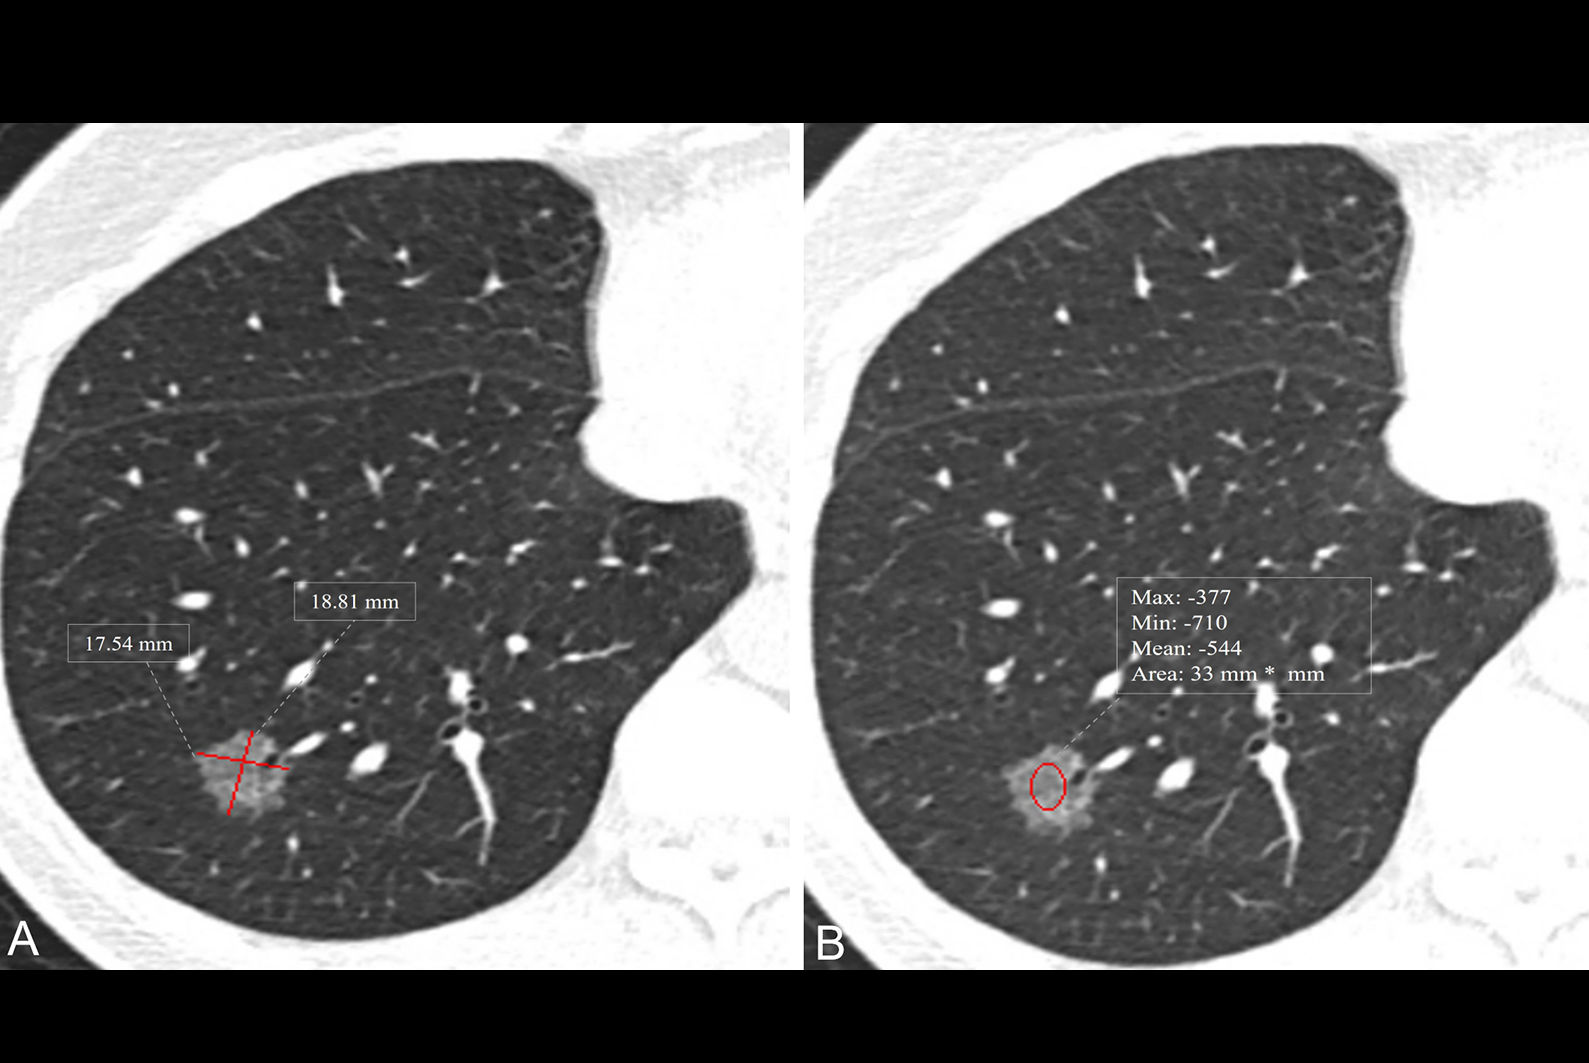

Chart from 2013 study plots CT scans from the emergency department, separating patients by increasing weight into columns from left to right. The results show that necessary alerts for smaller patients receiving relatively high doses (patients within red circle at left) would not have been generated. At the same time, too many alerts would be generated for larger patients (within red circle at right) who exceeded ACR diagnostic reference levels. The small red circle at center represents average-sized patients whose dose alarms would be appropriate. Image courtesy of Dr. Aaron Sodickson, PhD.Useful to a point